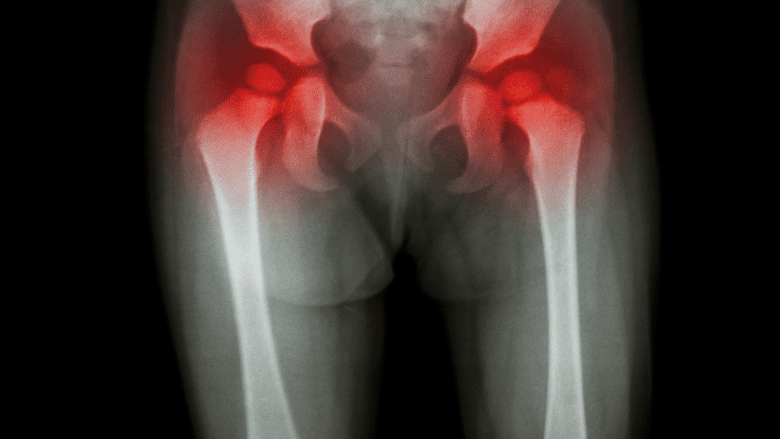

The most common symptoms of RA are pain, stiffness, and swelling in the feet, hands, knees, and hips.

RA inflammation in joints can usually be both observed (signs) and felt (symptoms). Inflammation is usually worse in the morning, lasting for an hour or more after getting out of bed. It may get better with light to moderate activity but still persist throughout the day.

RA inflammation can cause a joint to be:

- Painful

- Tender

- Swollen

- Stiff and difficult to bend or flex

- Warm to the touch

- Red in appearance

- Spongy or “boggy” when pressed

Joint involvement is usually symmetrical. For example, both the right and left wrists may be painful, stiff, and swollen.